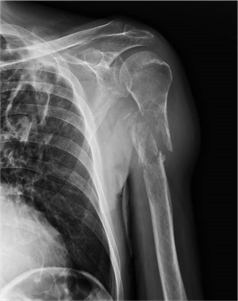

Es una lesión ósea frecuente en la infancia y es con diferencia la fractura patológica más frecuente en los niños que presentan una lesión ósea. La localización más frecuente es en el húmero proximal, seguido del fémur proximal. Las imágenes radiológicas mostrarán una fractura o una fisuración de la cortical del huso sobre una lesión radiolucente redondeada con o sin expansión de las corticales. El tratamiento habitual suele precisar únicamente la inmovilización ortopédica con yeso pues la consolidación correcta de la fractura es frecuente. En las fracturas desplazadas o en la extremidad inferior puede ser necesaria la cirugía.